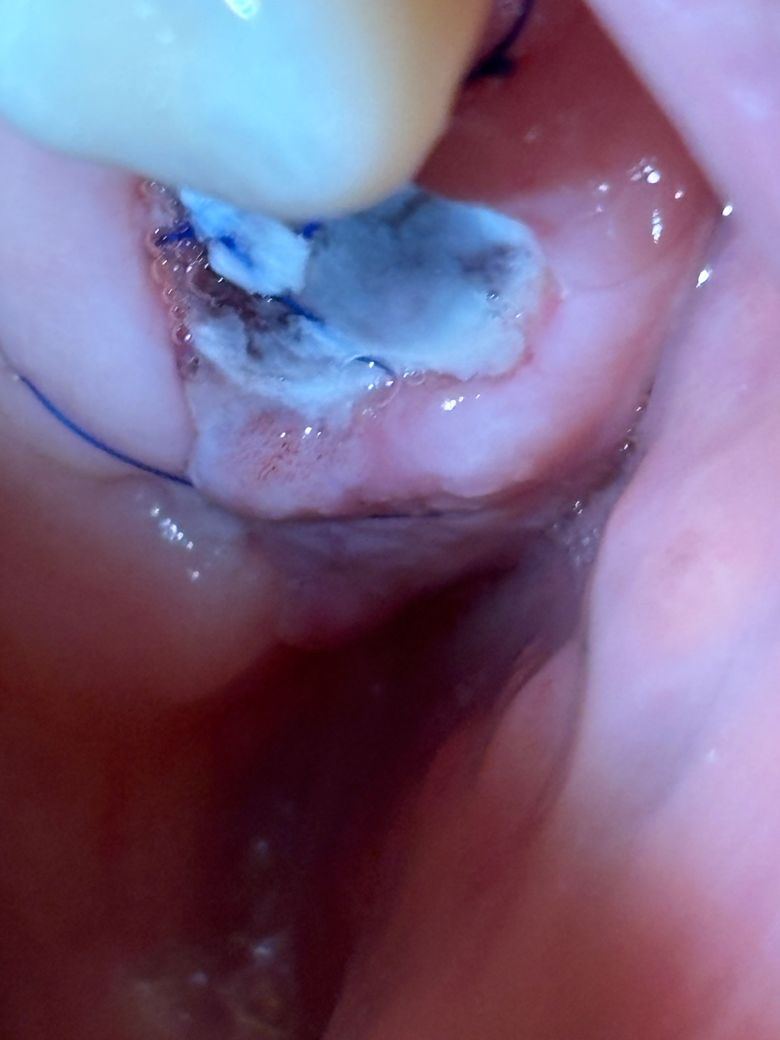

임플란트 기둥 식립 3일차 이거 괜찮나요?ㅠㅠ

어금니 두개 발치, 골이식 임플란트 식립 3일차입니다

조심해서 잘 관리 중이었는데 오늘 아침 양치하다 잘못해서 해당 부위를 건드렸는데요ㅠㅠ

식립부위를 살짝 막아놓은 부분 일부가 살짝 벌어지고 출혈이 살짝 있습니다ㅠㅠ

• 1번 째 사진

현재 사진상 살짝 건드려진 경우 문제가 되지 않기에 걱정하지 않아도 됩니다. 묻어나오는 피는 벧지말고 삼키는 것이 지혈에 도움이 되며, 양치시 해당부위는 피하고, 염증이 덧나는 것을 막기 위해 헥사메딘 가글액으로 가글하여 관리를 권합니다.

냉찜질을 하는 것도 도움이 됩니다.

만약 출혈이 지속되거나 악취, 고름 동반시에는 치과에 바로 방무을 권합니다.

식립부위를 살짝 막아놓은 부분 일부가 살짝 벌어지고 출혈이 살짝 있는 정도는 문제되지 않습니다.

사진상으로 크게 문제가 되는건 없습니다. 잘아물고 잇으니 자극만 가지 않도록 해주세요.

사진을 봤을 경우 수술한 부위가 부어있는것으로 보입니다. 해당부위를 자극하지 않으면 대부분 잇몸은 아물기때문에 가능하면 수술부위가 자극되지 않도록 하는것이 좋습니다.

잇몸 건드려서 살짝 피 난 것은 괜찮습니다. 지혈이 안되거나 그러진 않을 것 같고요. 잇몸 부위는 1~2주 정도는 예민한 상태이고 회복이 덜 되었을 것이니 조심히 관리해주시기 바랍니다.